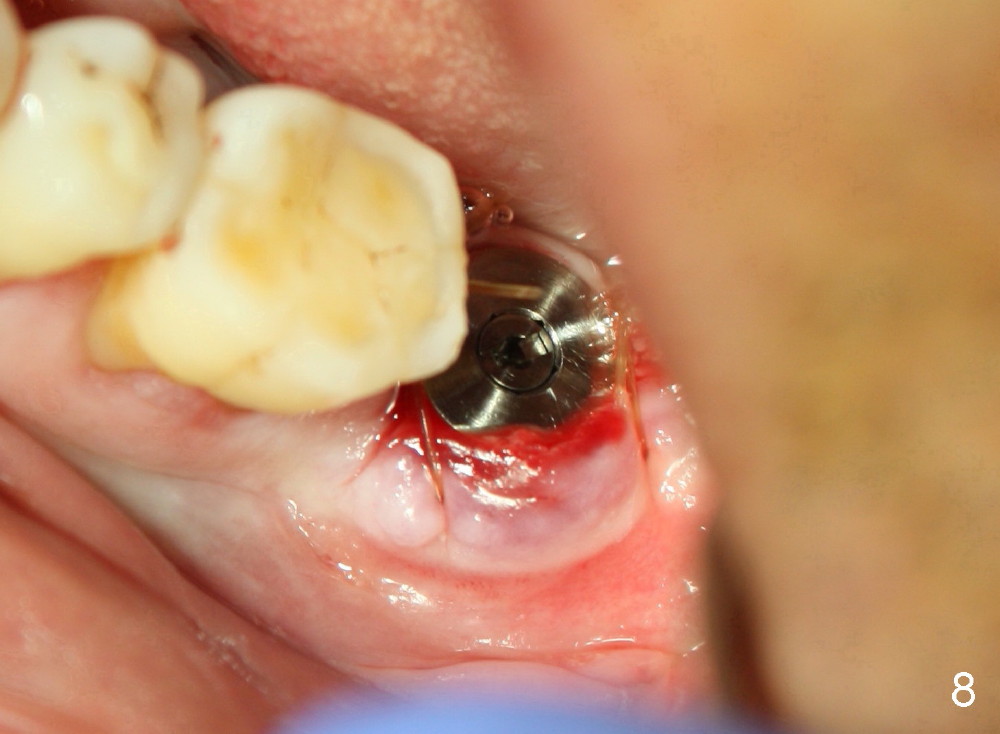

How about flatten the septum (Fig.4 white lines; from inset A (post extraction) to B)? When the septum is level with the mesial and distal sockets, a drill easily penetrates the middle of the socket (Fig.3 inset C). With strict control of depth, the osteotomy increases until a 6x14 mm tap gets initial binding to the socket (Fig.5: depth 11 mm). After increase in the depth by 1-2 mm, PA is taken with a 7x14 mm tap (Fig.6). There is a gap that the tap or the corresponding implant can engage further (between arrowheads). After increase in the diameter in the bottom of the osteotomy, a 7x11 mm implant is placed with insertion torque between 45 and 50 Ncm; the threads of the implant have tight contact with the bone (Fig.7). With the large diameter implant, the socket opening is closed without too much tension (Fig.8). The wound is protected with perio dressing. Postop there is no paresthesia. Pain is controlled by Hydrocodon/Acetaminophen. A long acting local anesthetic (Marcaine) should have been used immediately postop. Next morning, the patient is pain free. A short implant should be used in a critical area such as the lower 2nd molar where the inferior alveolar nerve is nearby. However, the implant is found unstable 1 month postop.